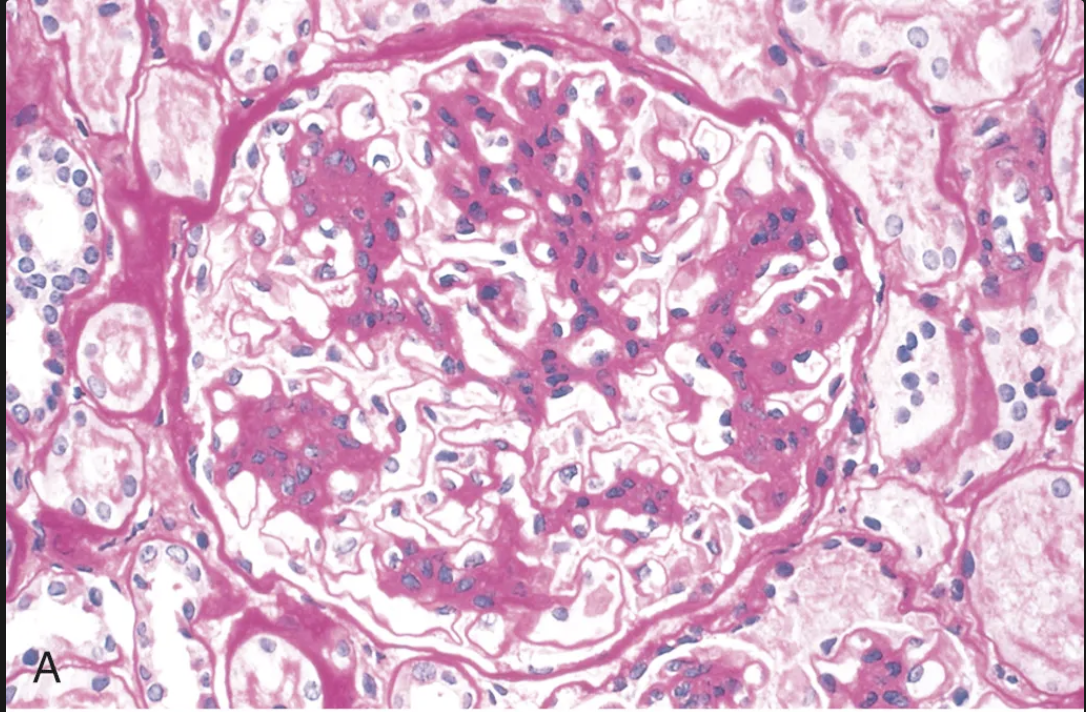

Qué se aprecia en la imágen y a que patologia está asociada?

Necrosis focal y segmentaria y formación de semilunas en el espacio de Bowman.

Enfermedad anti-GBM Good pasture syndrome